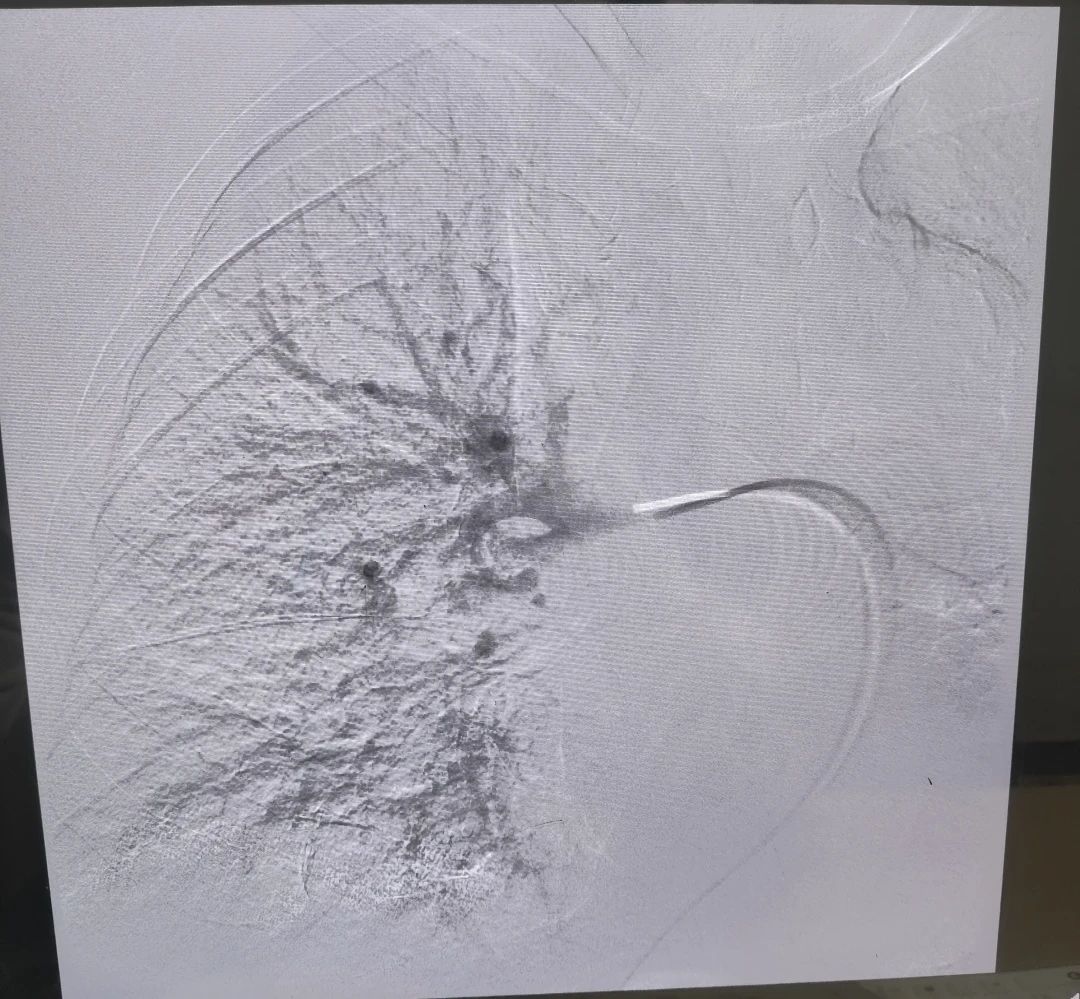

患者男性,69岁,2024年8月12日以“右侧下肢肿胀1周”在综合外科二病区就诊,后以“右下肢深静脉血栓形成”积极收住院治疗。次日查房时发现,患者血氧过低(约60%),我科援藏专家谢文涛主任考虑患者存在肺栓塞可能,立即主持科内术前讨论后建议立即行肺动脉造影介入治疗。经过40分钟的紧急手术治疗,左肺动脉主干血栓完全清除,为预防后期再次出现肺栓塞,同时下腔静脉置入可回收滤网。患者自身症状明显缓解,患者及家属对治疗效果非常满意,并于两周后,8月28日再次入住综合外科二病区,顺利取出可回收滤器。